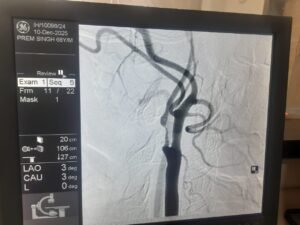

एक साल पहले प्रेम सिंह को स्ट्रोक हुआ था, जिससे उनके शरीर के बाएं हिस्से में कमजोरी आ गई थी। हालिया जांच में पता चला कि उनकी दाहिनी कैरोटिड आर्टरी में 95-99% तक गंभीर रुकावट थी, जो भविष्य में फिर से स्ट्रोक का बड़ा कारण बन सकती थी।

डॉक्टरों की मल्टीडिसिप्लिनरी टीम ने स्टेंट लगाने के बजाय सर्जरी को अधिक सुरक्षित विकल्प माना, क्योंकि रक्त नली में मौजूद प्लाक बहुत नरम और नाजुक था, जो टूटकर मस्तिष्क तक पहुंच सकता था। इसलिए Carotid Endarterectomy की सिफारिश की गई, जिसमें गर्दन की धमनी को खोलकर जमा प्लाक को सावधानी से निकाला जाता है।

सर्जरी डॉ. रोहित चौहान (सर्जन, जीबी पंत अस्पताल दिल्ली से प्रशिक्षित) द्वारा की गई। ऑपरेशन के दौरान Pruitt–Inahara Shunt जैसे विशेष उपकरण का उपयोग किया गया, जिससे सर्जरी के दौरान मस्तिष्क में रक्त प्रवाह निरंतर बना रहा और स्ट्रोक का खतरा न्यूनतम रहा। सर्जरी में बड़े, नरम और वसा युक्त प्लाक के टुकड़े निकाले गए, जिससे टीम का निर्णय पूरी तरह सही साबित हुआ।